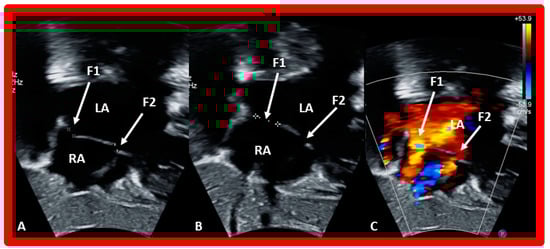

9. Follow-Up after Device Occlusion